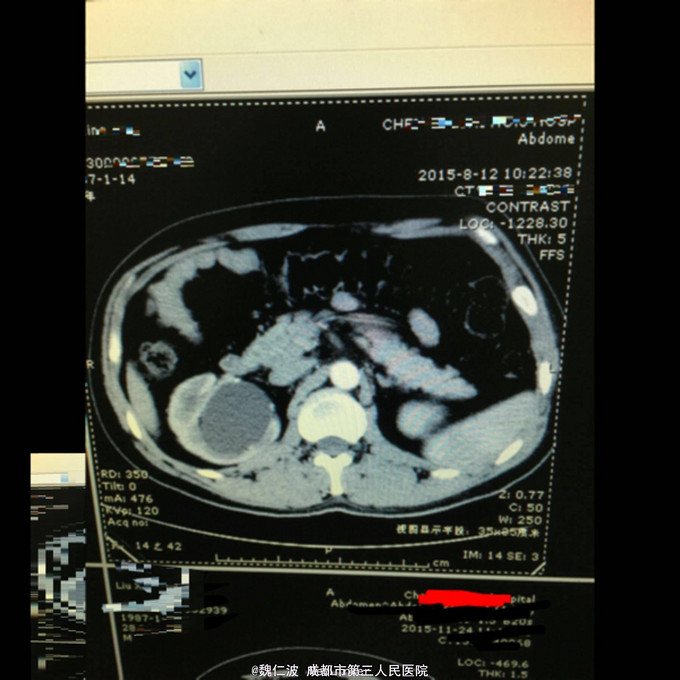

右侧输尿管结石碎石术后3月,发现右侧输尿管上段闭锁4天 3月前因右侧输尿管上端结石行输尿管软镜钬激光碎石,术后恢复可,但拍石稍差,1月后取支架管,术后2月复查右侧肾积水1厘米,3月复查积水5Cm,外院行右肾穿刺造瘘术,发现右侧输尿管上端闭锁,遂来我院。

造瘘管通畅,尿液淡黄。余无特殊。 辅助检查尿常规正常,右侧肾盂尿白细胞2+。

右侧输尿管上端闭锁,右肾结石,右侧输尿管上端结石 经抗感染治疗后,行开放狭窄段切除,输尿管吻合术,安置F8输尿管支架管。